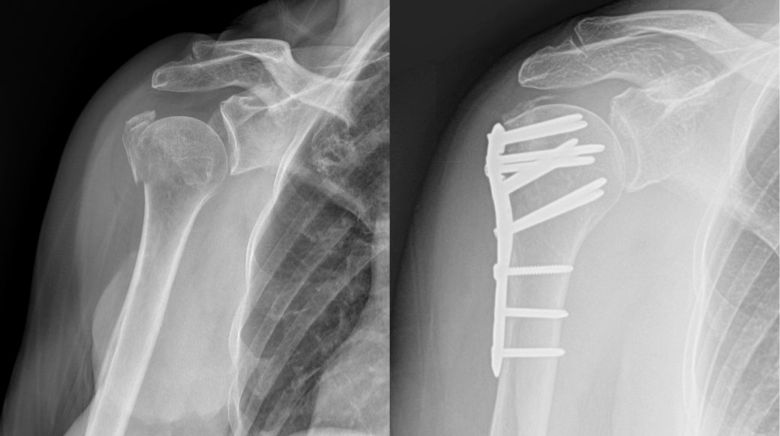

Clavicle fractures occur most frequently after a direct fall on the shoulder. They are especially common in young males. Dirt biking accidents are a frequent mechanism. They present with pain and swelling over the clavicle. In general, greater than 2 cm of shortening or 100% displacement increases the chances of non-union, decreased shoulder strength, decreased endurance, and altered scapular mechanics with pain. Many clavicle fractures can be treated without surgery; however, patients with greater than 2 cm of shortening or greater than 100% displacement typically have better short term outcomes with surgical fixation.

Clavicle radiographs demonstrating a multi-fragmented right clavicle fracture (left image), treated with open reduction and internal fixation (right image)